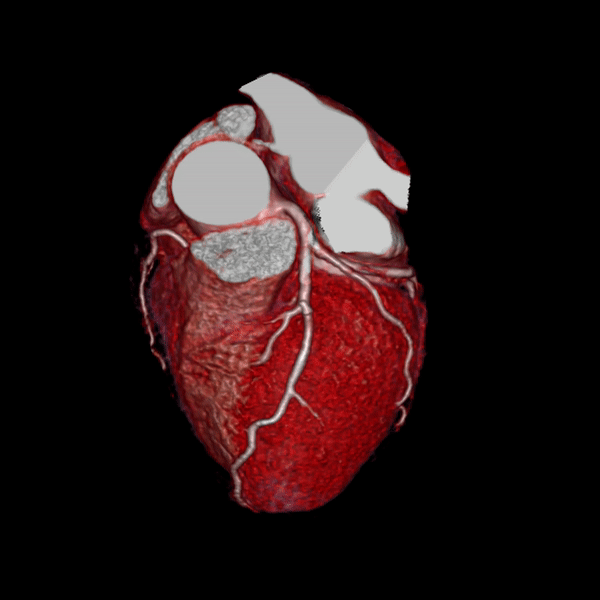

Đặc biệt, thế mạnh của máy CT 160 lát cắt Aquilion Prime SP là khả năng chụp tim – mạch vành và đồng bộ nhịp tim. Công cụ SURECardio thông minh được mã hóa với kinh nghiệm của hàng nghìn ca khám tim, đảm bảo các thông số quét thích ứng chính xác với bệnh nhân cho phép chụp và dựng hình hình ảnh tim – mạch vành ngay cả với những bệnh nhân có rối loạn nhịp tim như ngoại tâm thu, nhịp nhanh, loạn nhịp,… Đây là một phương pháp khảo sát hệ thống mạch vành để chẩn đoán hẹp, xơ vữa một cách chính xác mà không cần xâm lấn.

Hình ảnh dựng hình tim và mạch vành của máy Aquilion Prime SP